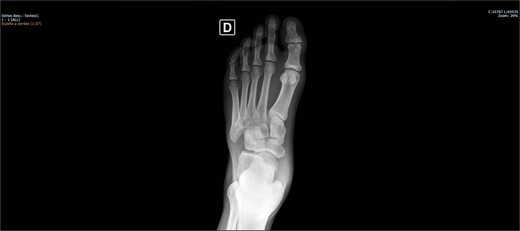

The patient was placed on the surgical table in the supine position, anesthetized with spinal anesthesia, and given prophylactic antibiotic therapy with 2 g of cefazolin. After exsanguination of the lower limb, a dorsolateral incision was made on the foot over the cuboid bone and deepened through the layers until complete visualization of the cuboid bone was achieved. There was an interposition of ligamentous structures, such as the calcaneocuboid ligament, dorsal cuneocuboid ligament, and dorsal tarsometatarsal ligaments. After removing all structures that were interposed and preventing reduction, the cuboid was reduced easily, but instability was observed. Due to the instability found, percutaneous fixation was performed with three Kirschner wires: the first extending from the fourth metatarsal to the calcaneus, traversing the cuboid; the second from the fifth metatarsal to the cuboid; and the third from the cuboid to the calcaneus, from anterior-dorsal to posterior-plantar (Figs 3 and 4). After complete fixation, the stability of the cuboid was observed, maintaining it in the correct position, confirmed with fluoroscopy during surgery.